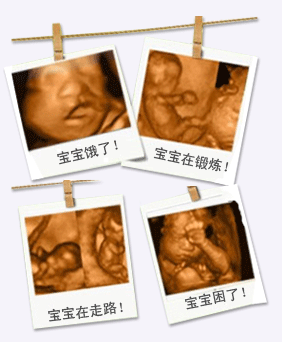

四維彩超拍攝圖片